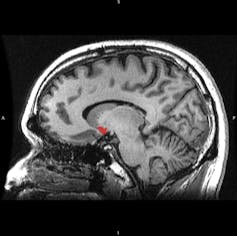

Evolution has resulted in the mesolimbic pathway, a brain system that deciphers these natural rewards for us. When we do something pleasurable, a bundle of neurons called the ventral tegmental area uses the neurotransmitter dopamine to signal to a part of the brain called the nucleus accumbens. The connection between the nucleus accumbens and our prefrontal cortex dictates our motor movement, such as deciding whether or not to taking another bite of that delicious chocolate cake. The prefrontal cortex also activates hormones that tell our body: “Hey, this cake is really good. And I’m going to remember that for the future.”

Like drugs, sugar spikes dopamine release in the nucleus accumbens. Over the long term, regular sugar consumption actually changes the gene expression and availability of dopamine receptors in both the midbrain and frontal cortex. Specifically, sugar increases the concentration of a type of excitatory receptor called D1, but decreases another receptor type called D2, which is inhibitory. Regular sugar consumption also inhibits the action of the dopamine transporter, a protein which pumps dopamine out of the synapse and back into the neuron after firing.